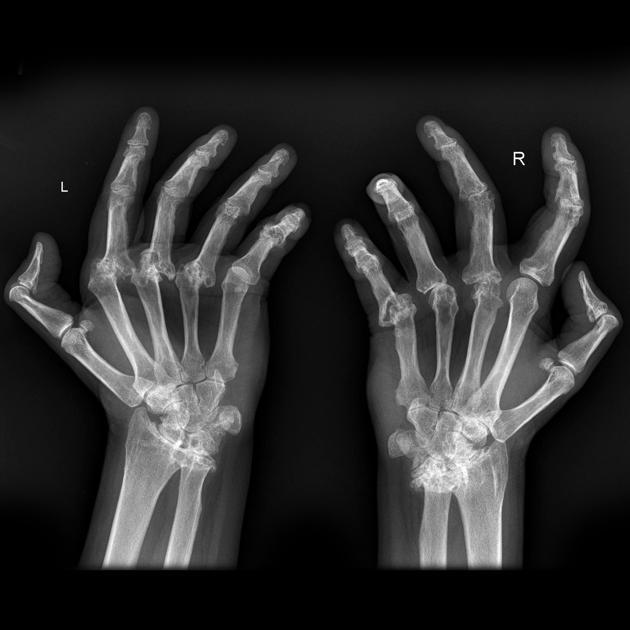

What are the features and pathology depicted

rheumatoid arthritis

features on x-ray (LESS)

also may see deformity + deviations e.g. ulnar deviation